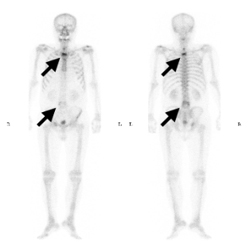

흉부 단순촬영(X-ray), 복부골반 전산화단층촬영(CT), 자기공명영상(MRI), 뼈동위원소검사(Bone scan)를 이용하게 됩니다. 국소 연부조직의 침윤과 림프절의 전이 여부는 전산화단층촬영(CT) 혹은 자기공명영상(MRI)을 통해 진단하고, 특히 요도암에 의한 음경 해면체의 침윤을 확인하는 데는 자기공명영상(MRI)가 유용합니다. 그 외 요도암의 국소 진행으로 직장의 침윤이 의심되는 경우에는 에스결장 내시경을 시행할 수 있습니다. 상부요로를 평가하기 위해서는 경정맥 신우조영술(IVP)을 시행합니다.

경추, 흉추 및 요추에 다발성 골전이 병변이 관찰됩니다.

[ 경추, 흉추, 및 요추에 다발성 골전이 병변이 관찰되는 뼈동위원소 검사 ]